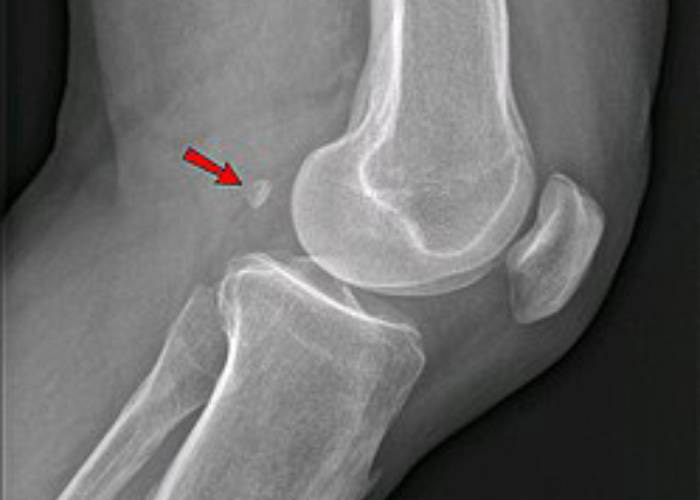

اخیرا دانشمندان بریتانیایی گزارش کرده‌اند استخوانی که قبلا تصور می‌شد در جریان تکامل در‌ حال ناپدیدشدن باشد، درحال‌بازگشت است. این استخوان کوچک که فابلا (لوبیای کوچک) نامیده می‌شود، اگر وجود داشته باشد، در پشت زانو قرار گرفته است. طبق برآورد دانشمندان، احتمال اینکه فردی در سال ۲۰۰۰ این استخوان را داشته باشد، تقریبا ۳.۵ برابرِ احتمال داشتن آن در سال ۱۹۰۰ است و البته، هدف دقیق حضور آن همچنان معما است.